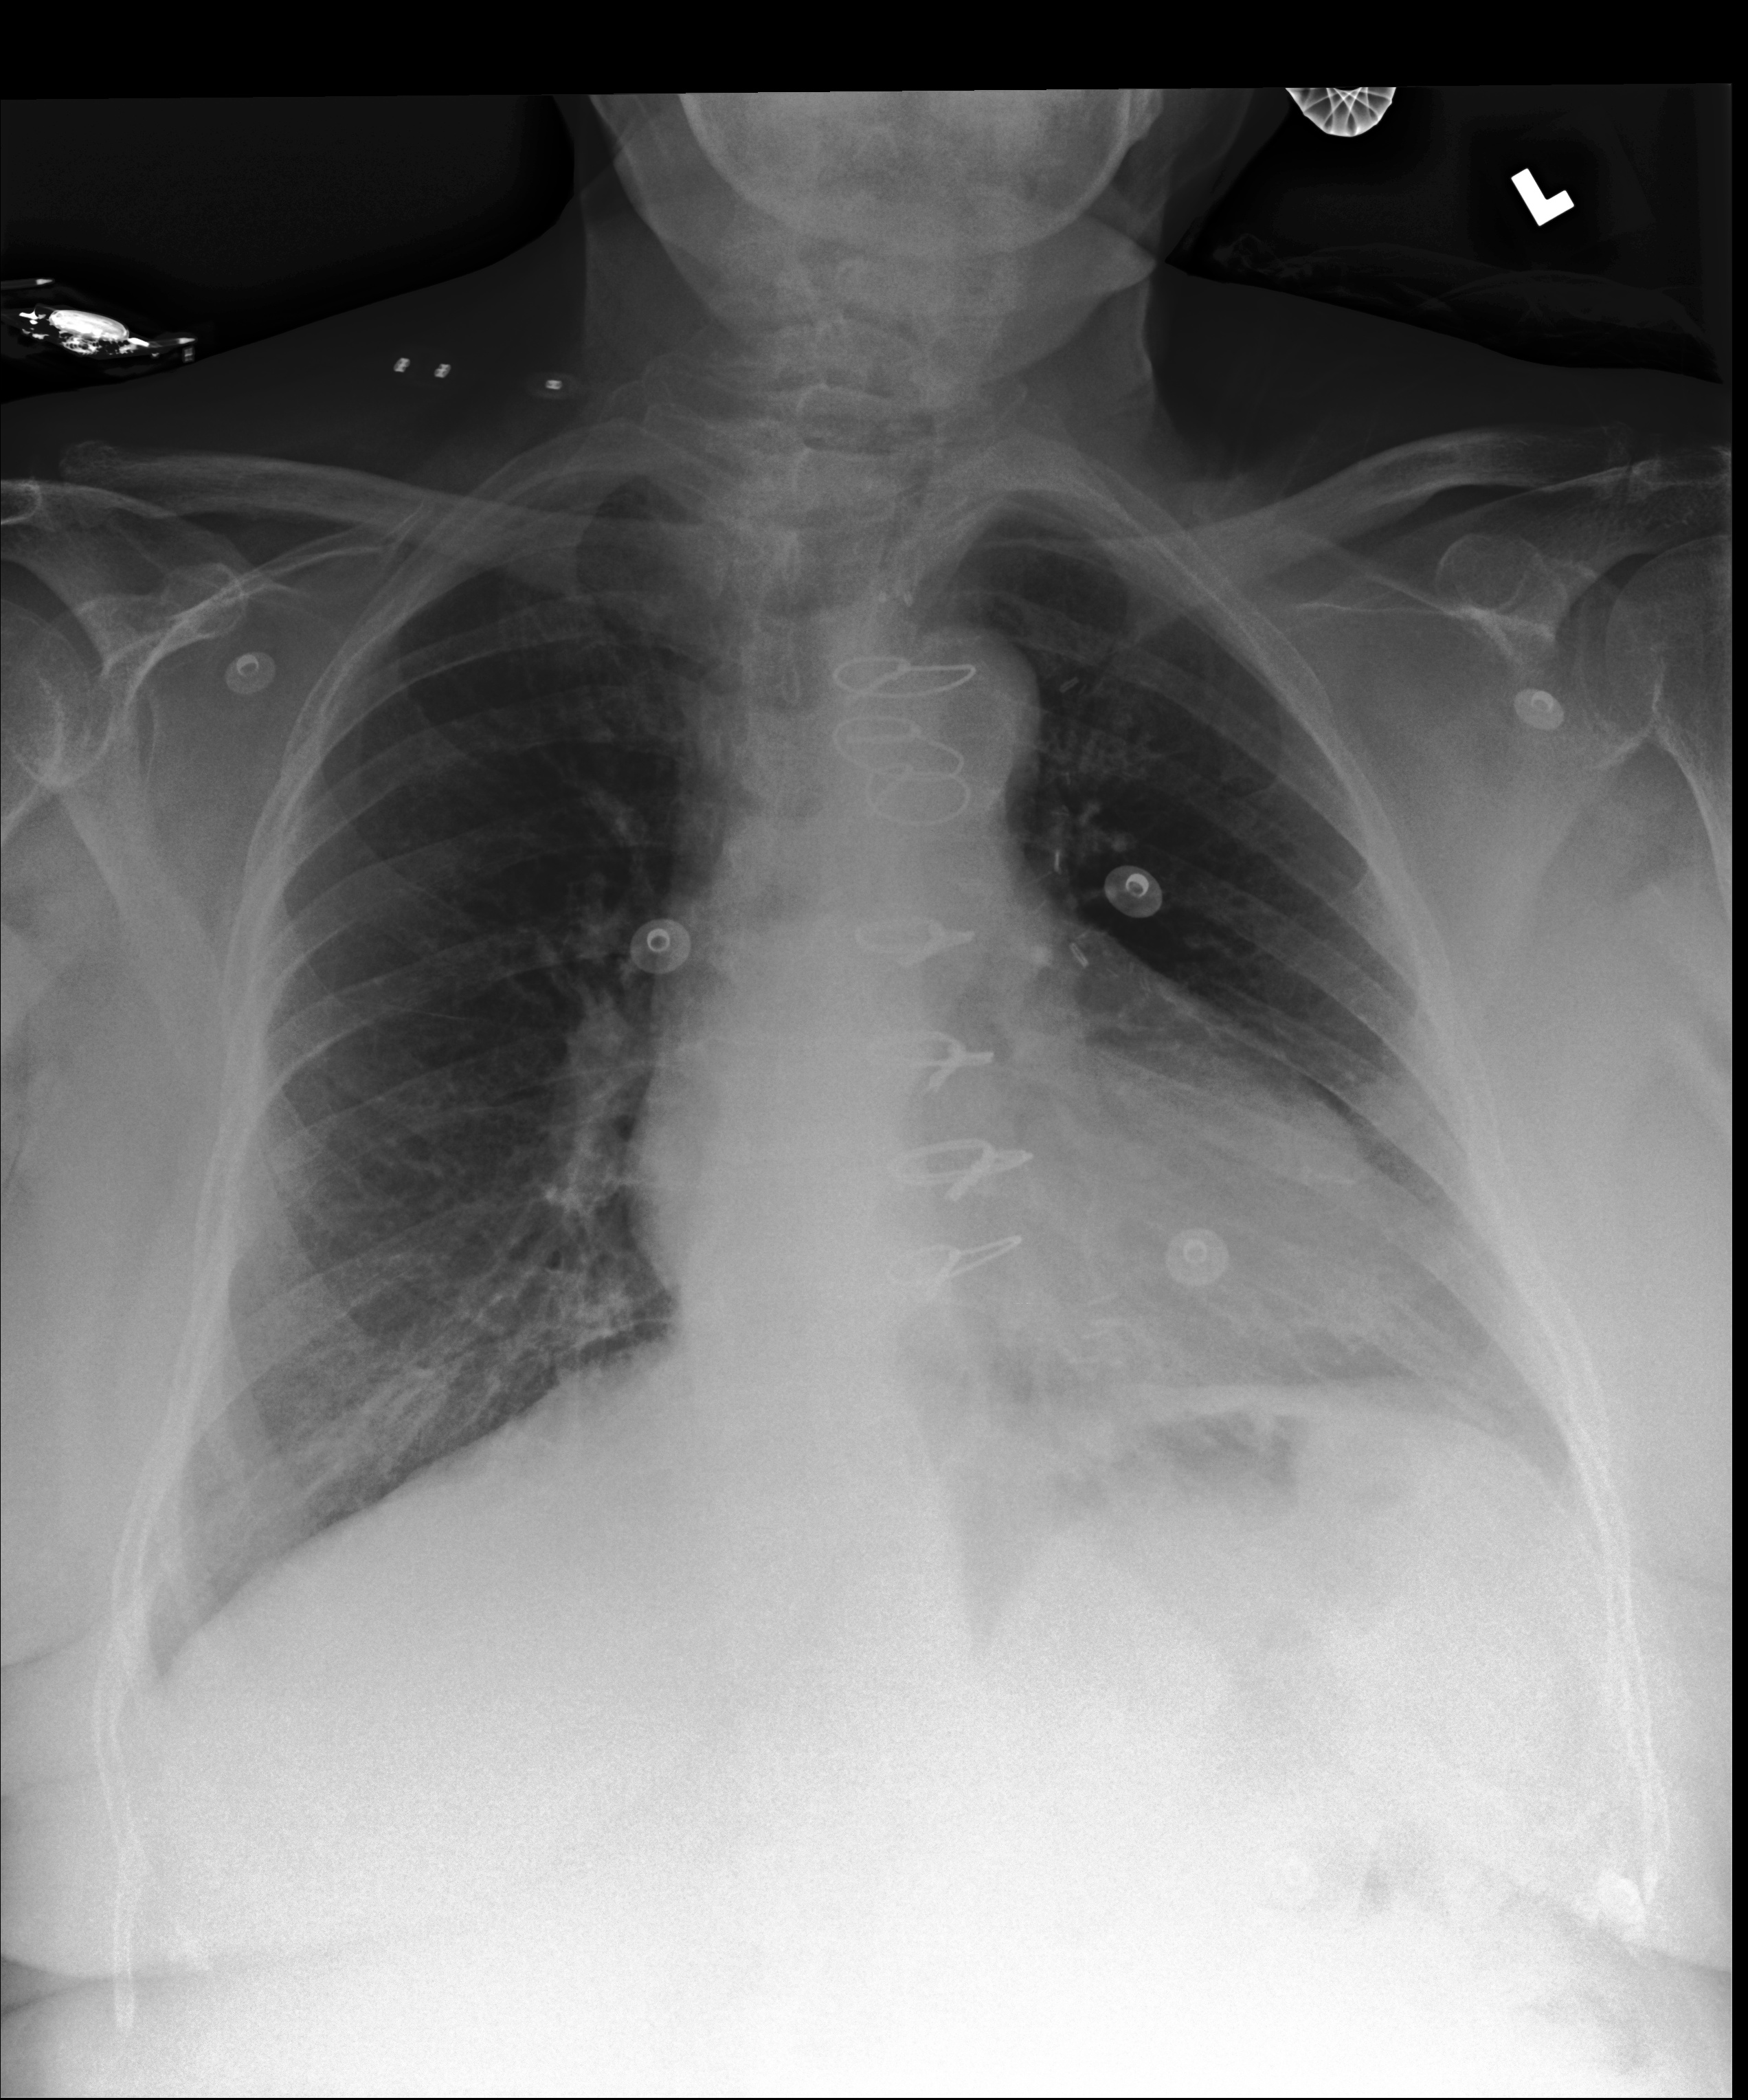

The results are shown in Table 2. Also, an example comparison of generated text from JRadiEvo and the ground truth on the test data is shown in Table 3.

| Example 1 | ||||||||

|

| Example 2 | ||||||||

| Example 3 | ||||||||